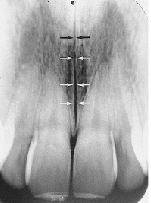

Incisive Foramen

small round radiolucent area between roots of max centrals

(radiolucent)

Superior Foramina of Incisive Canal

two tiny openings on the floor of the nasal cavity

Median Palatal Suture

thin radiolucent line between roots of max centrals

Nasal Septum

vertical radiopaque divider in the nasal cavity

(radiopaque)

Floor of Nasal Cavity

dense radiopaque band of bone above the max incisors

Anterior Nasal Spine

v-shaped radiopaque area at base of nasal septum